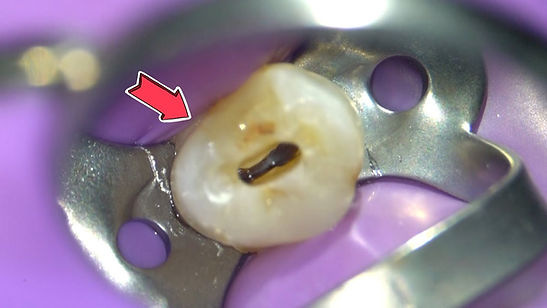

The Clarity of Microscope-Enhanced Dentistry

Experience dentistry with a new level of detail. Microscope-enhanced dentistry utilizes powerful magnification to provide an incredibly clear and magnified view of the treatment area. This advanced approach allows Dr. Sukumar to detect even the smallest issues, perform intricate procedures with pinpoint accuracy, and preserve more of your natural tooth structure. The benefits are clear: more precise diagnoses, minimally invasive treatments, reduced discomfort, and ultimately, superior long-term results for your smile.